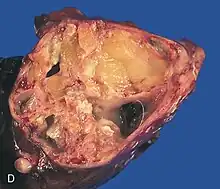

- Immature (maligne)

- Monodermique ou spécialisé

Les tératomes de l'ovaire

Les tératomes immatures de l’ovaire, souvent détectés à l'échographie, TDM ou IRM[21] sont potentiellement malins tout comme les tératomes testiculaires, qui sont généralement moins bien différenciés (donc avec un pronostic plus sombre). Des effets hormonaux, systémiques ou éloignés (ex. : encéphalite limbique paranéoplasique, encéphalite paranéoplasique anti-NMDAr)[22] sont possibles. Les métastases sont rares mais possibles (ex. : métastases neuroïdes matures d’un tératome ovarien[23]). Après ablation, des récidives sont possibles[24].